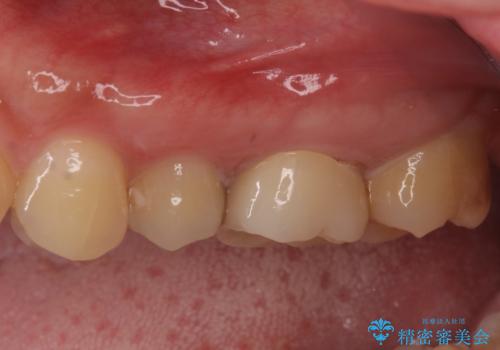

- 奥歯の虫歯と銀歯を気にして来院された患者様です。

セラミックインレーおよびセラミッククラウンによる治療を希望されましたが、虫歯となっている歯は神経近くにまで蝕まれていたため、長期的な予後を鑑みて、PGAインレー(プラチナゴールドインレー)にて修復することとしました。

ゴールドインレーを装着するまでは、金属色が目立ってしまうのではないかと心配されていましたが、表からは見えない位置にあること、銀歯と異なり目立つ色ではないことから、審美的な問題はありませんでした。